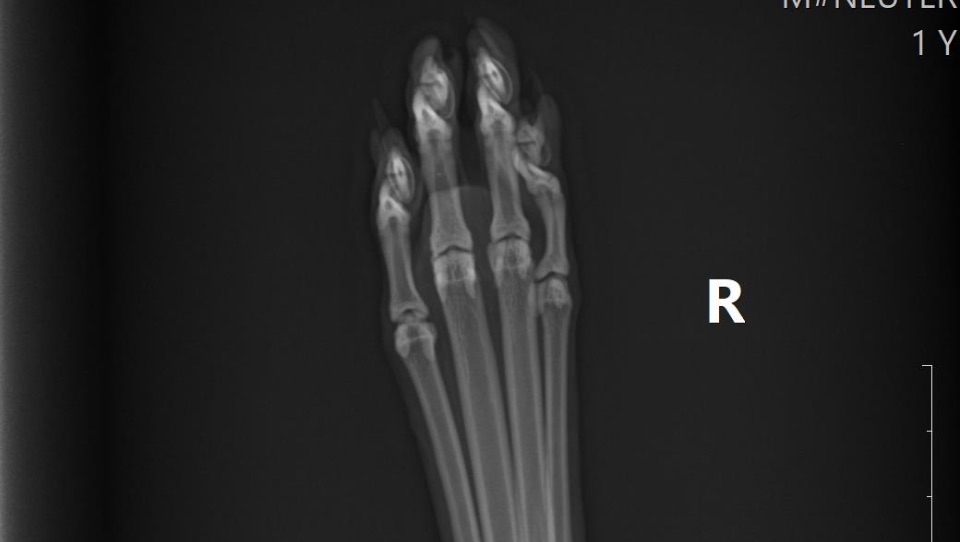

Xrays ⬇️

We rushed him to the vet the next day. That alone cost nearly $700, which completely drained us. They did X-rays and gave him pain meds, and the next day we got the news: Puddles has a fractured femur near the hip, and he needs a surgery called an FHO (femoral head ostectomy) to be able to walk normally again without pain.